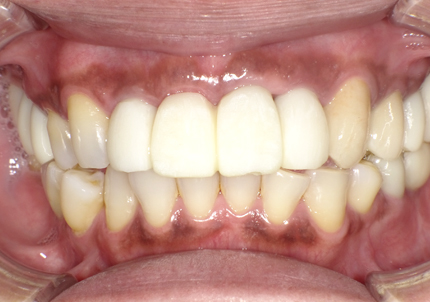

22.最終補綴物完成・装着口腔内写真(2021年1月)

23.自然な形態のインプラント歯頚部

適切な治療計画と治療技術を有することで、このような自然な形態のインプラント歯頚部を形成することができます。

24.口腔内写真

【 2018年 術前 】

【 2025年5月 現在 】